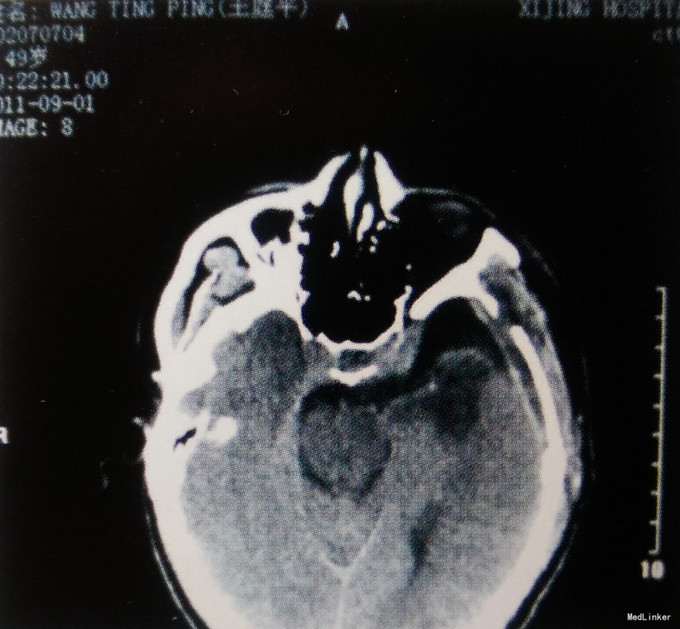

患者,男,49岁。主因头痛伴视力下降半年入院。 患者于半年前无明显诱因出现间断性头痛,钝痛,左侧额颞部为甚,同时伴左眼视物模糊。头颅MRI检查:左侧鞍旁见一类圆形病变,大小约5.7cmх4.1cmх4.6cm,边界清楚,三脑室前部受压变形,增强扫描明显均匀强化,考虑为脑膜瘤。发病以来,精神、饮食差,大小便正常,恶心、呕吐严重,无抽搐、昏迷。体重无明显变化。

查体:体温36.9℃,脉搏78次/分,呼吸20次/分,血压130/80mmHg。意识清楚,双侧瞳孔等大同圆,直径约3.0mm,直接、间接对光反射均灵敏,右眼视力为0.8,左眼视力仅有光感;四肢肌力、肌张力正常,余神经系统查体无明显异常。 术前影像学检查颅脑MRI:左侧鞍旁见一类圆形病变,大小约5.7cm×4.1cm×4.6cm,边界清楚,三脑室前部受压变形,增强扫描明显均匀强化,考虑为脑膜瘤。

入院诊断:左侧鞍旁巨大脑膜瘤。 治疗:手术切除。患者仰卧位,左侧翼点入路,见肿瘤侵犯左侧颈内动脉、大脑前动脉、大脑中动脉、左侧海绵窦,严重压迫视神经和视交叉,肿瘤体积巨大,边界清楚,呈灰褐色,质地软,有大量坏死出血灶,沿肿瘤边界分离,电凝主要供瘤血管后,显微镜下全切肿瘤。